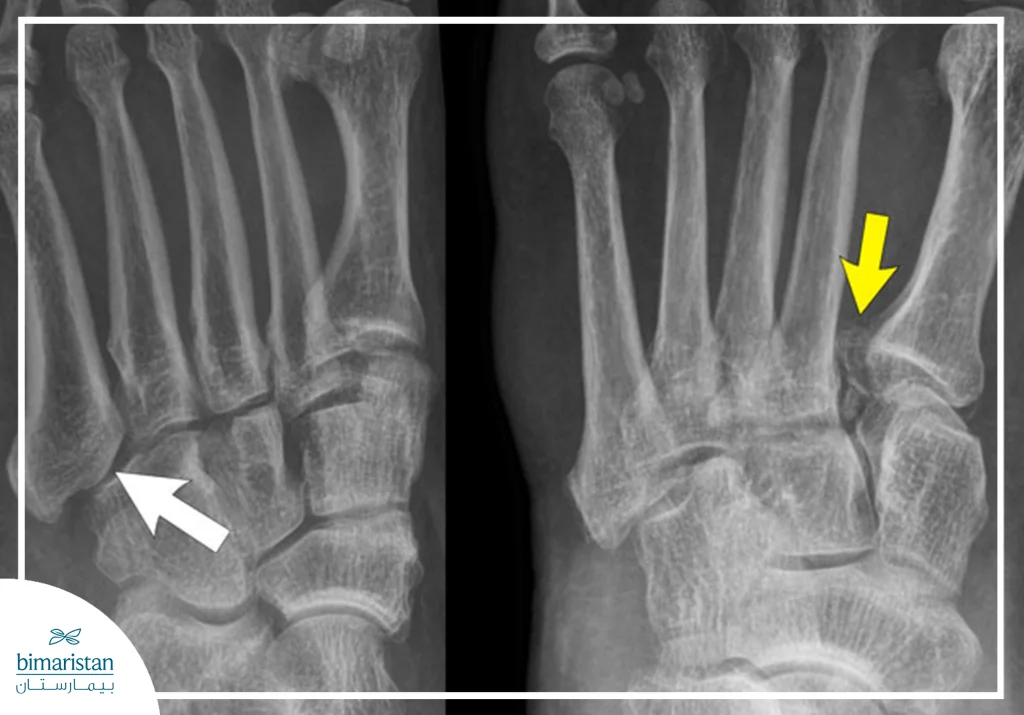

X-ray imaging

X‑ray imaging is considered the primary method for diagnosing most cases of foot fractures, as it provides precise visualization of the fracture site and helps determine whether the fracture is closed or open, simple or multiple. It is typically used as the first option following clinical examination and is essential for guiding the physician’s decision regarding immobilization or surgical intervention. In many cases, imaging is performed from multiple angles to obtain a comprehensive view of the bone structure.

Computed Tomography (CT)

This examination is used when X‑rays are insufficient to reveal bone details accurately, particularly in complex foot fractures such as calcaneal fractures or fractures of the subtalar joint. CT provides three‑dimensional images that allow the physician to assess the degree of bone fragmentation and the alignment of bone fragments. It is considered an essential tool before surgical planning or when a detailed evaluation of post‑fracture complications is required.